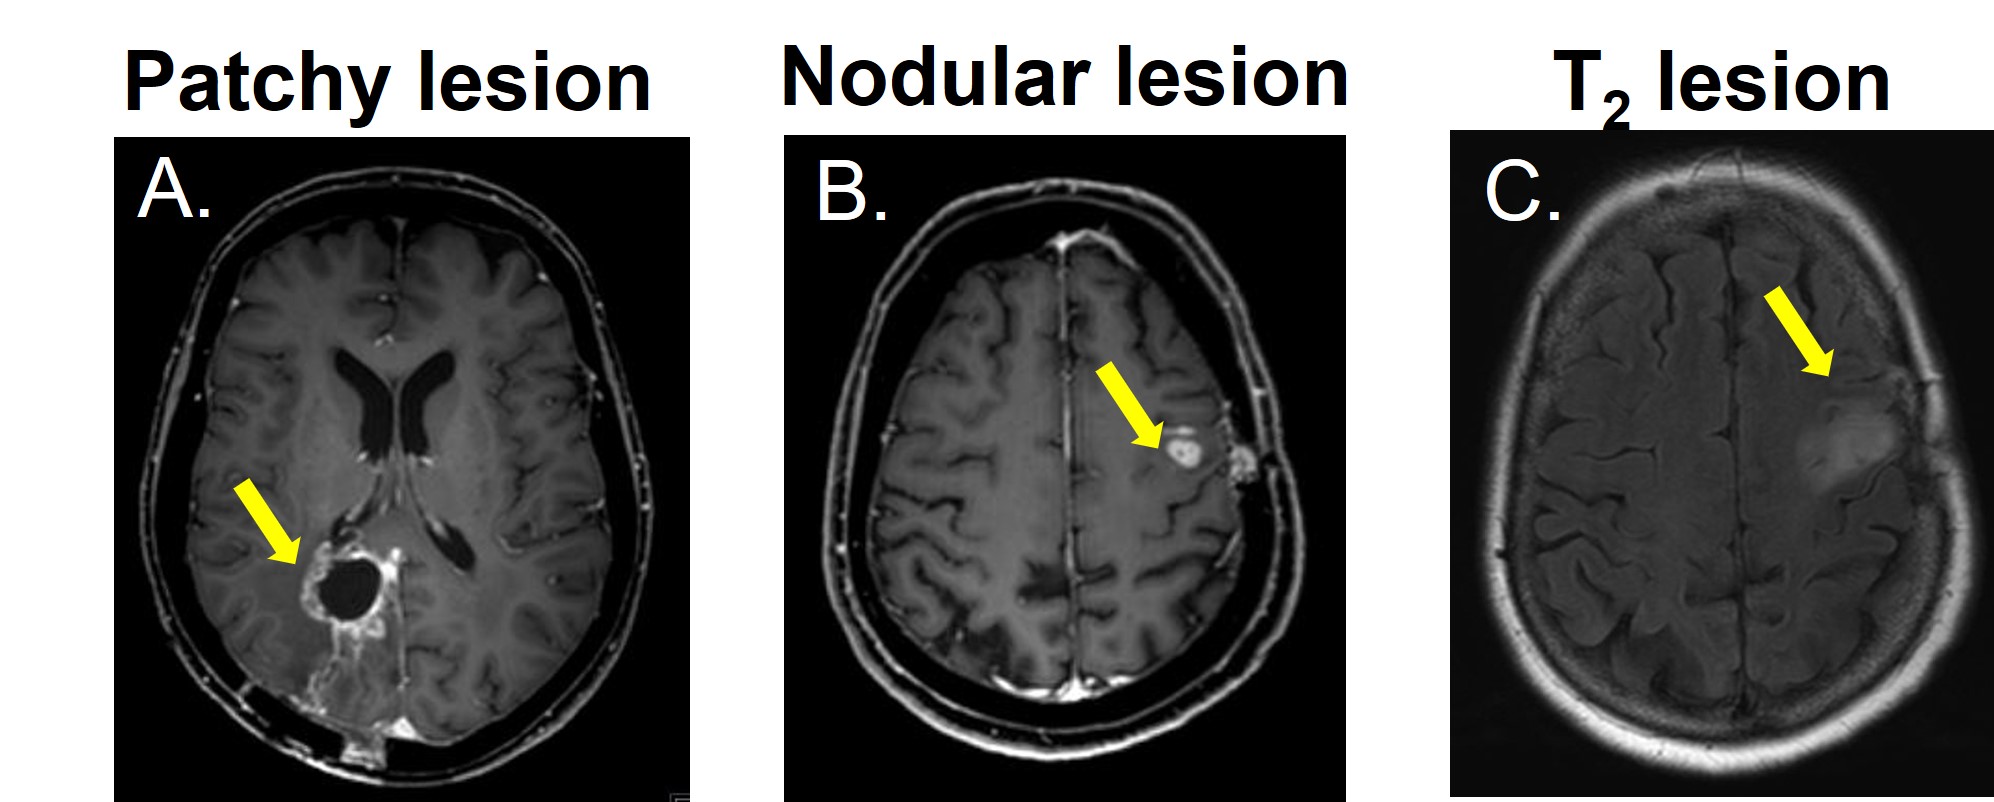

Figure1 shows examples of patchy enhancing lesions (PE), nodular enhancing lesions (NE), and a T2-hyperintense lesion. Figure2 illustrates the output of the clustering analysis as a heatmap where patients and subsequently clusters of patients are grouped based on similar tumor characteristics. Most markers differed significantly per cluster (p≤0.05). Few exceptions included the tumor location parameters (except the temporal region), the presence of NE, the DSC perfusion in T2-hyperintense lesions and the eccentricity of enhancing and T2-hyperintense lesions (p>0.05). We then chose the markers that most clearly differentiated the 4 clusters to provide a summary illustration (figure3). For example, cluster 1 and 2 have similar incidence of PE and NE. Interestingly cluster 1 has predominantly hyperperfused PE whereas cluster 2 has mostly NE hyperperfused lesions. Clusters 3 and 4 have mostly only NE and PE respectively, as well as smaller tumor volumes and mostly isoperfused tumor lesions . Figure4 shows that the OS is different for each cluster and had a substantial effect size especially between cluster 2 with the lowest OS (158days±5months) and cluster 4 with the largest OS (329days±11months). However, there was no significant between-group difference in OS and tumor progression rates at 9 months (p>0.05).

Figure 1. An example of A. patchy enhancement, B. nodular enhancement and a C. T2-hyperintense lesion.